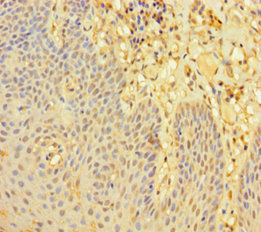

Immunohistochemistry of paraffin-embedded human tonsil tissue using CSB-PA013009HA01HU at dilution of 1:100